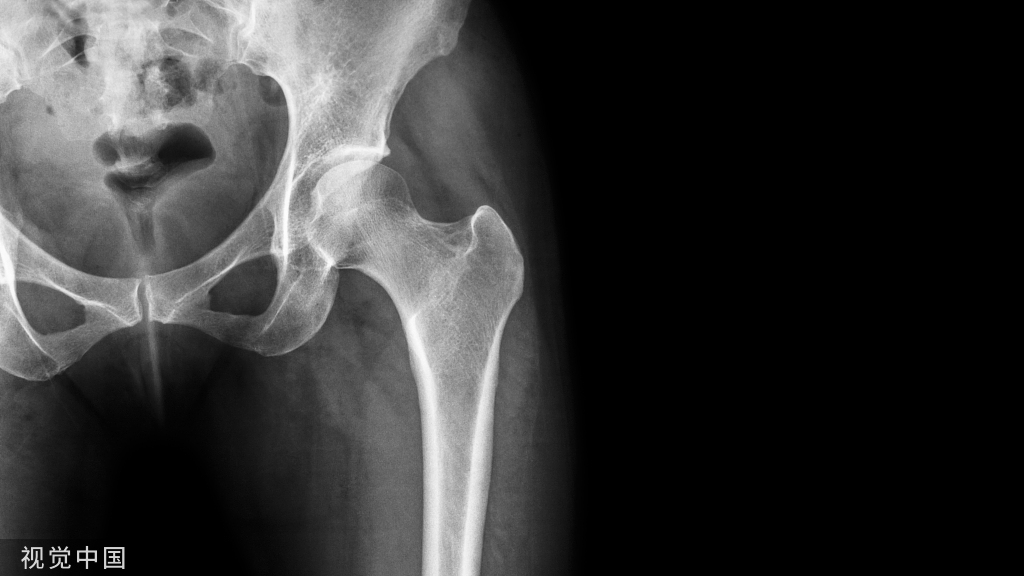

慢性疼痛:持续3个月的疼痛。 主要受慢性退行性病变的影响或由神经损伤造成,如骨关节炎引起的关节疼痛、脊柱源性疼痛、术后慢性持续性疼痛和癌性疼痛等。国外对于年龄>45岁的成年人调查研究发现,多关节疼痛发生率高达68%。膝关节置换术后慢性疼痛发生率为10%~34%,髋关节置换术后慢性疼痛发生率为7%~23%;约7%全膝关节置换患者和2%全髋关节置换患者术后疼痛程度甚至比术前更严重。

骨科围手术期疼痛包括原发疾病和手术操作引起的疼痛,或两者兼而有之。